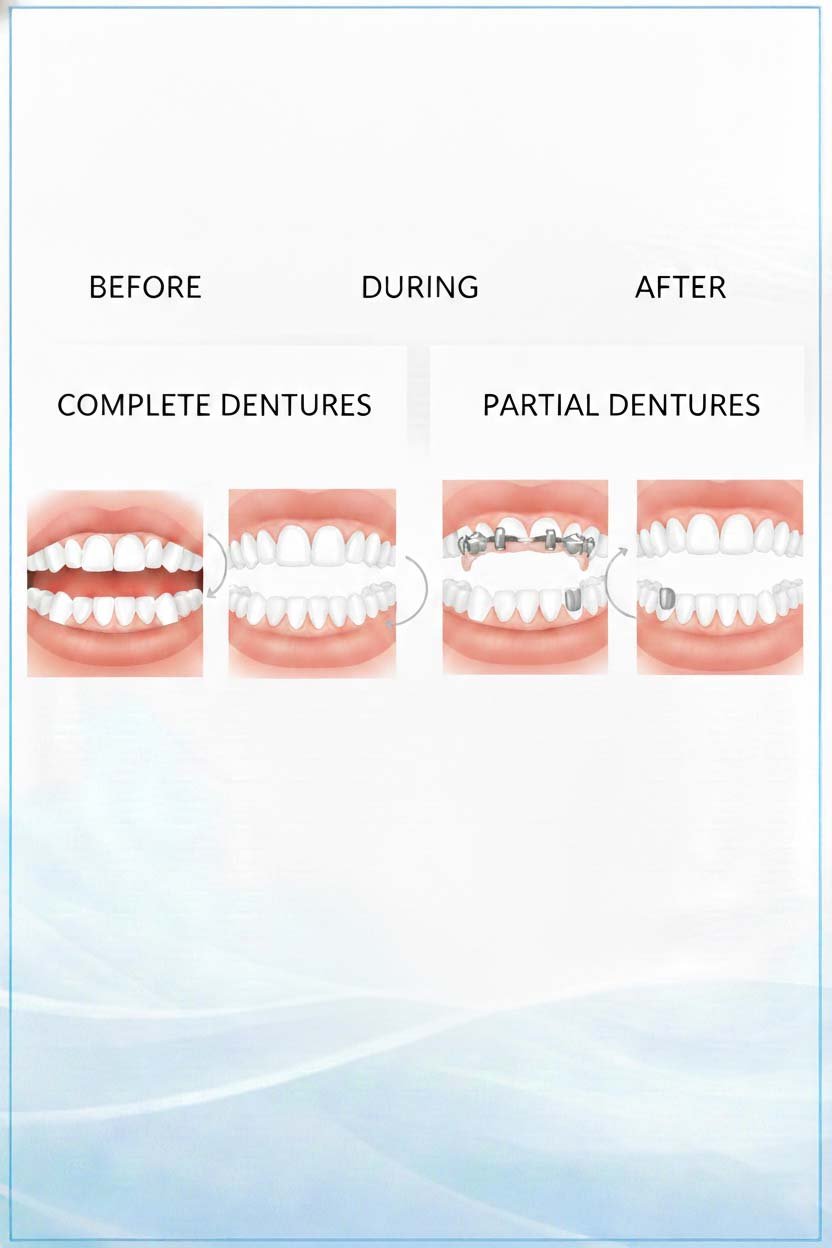

Complete & Partial Removable Dentures